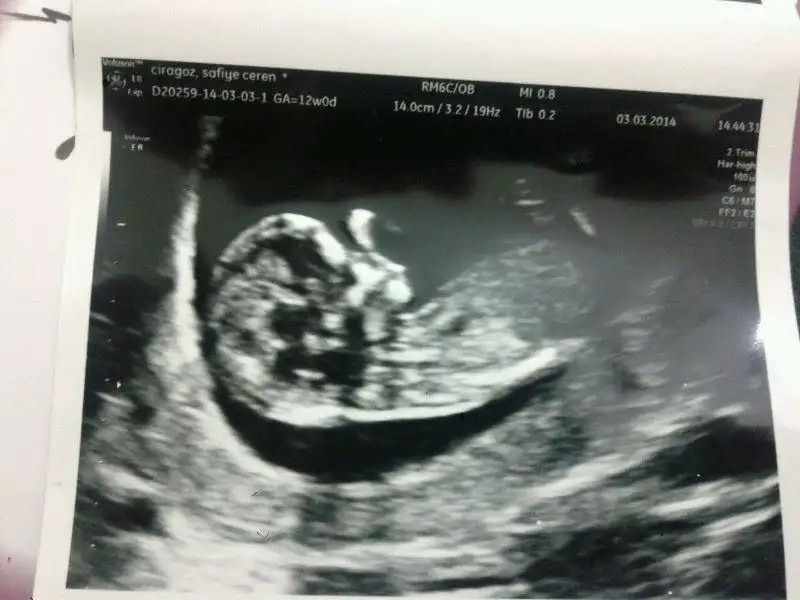

Bebegim 12+6 gunluk burada. Doktor cinsiyeti icin erken dedi. Elimizdeki tek resim bu.

Yorumlarinizi esirgemeyin.